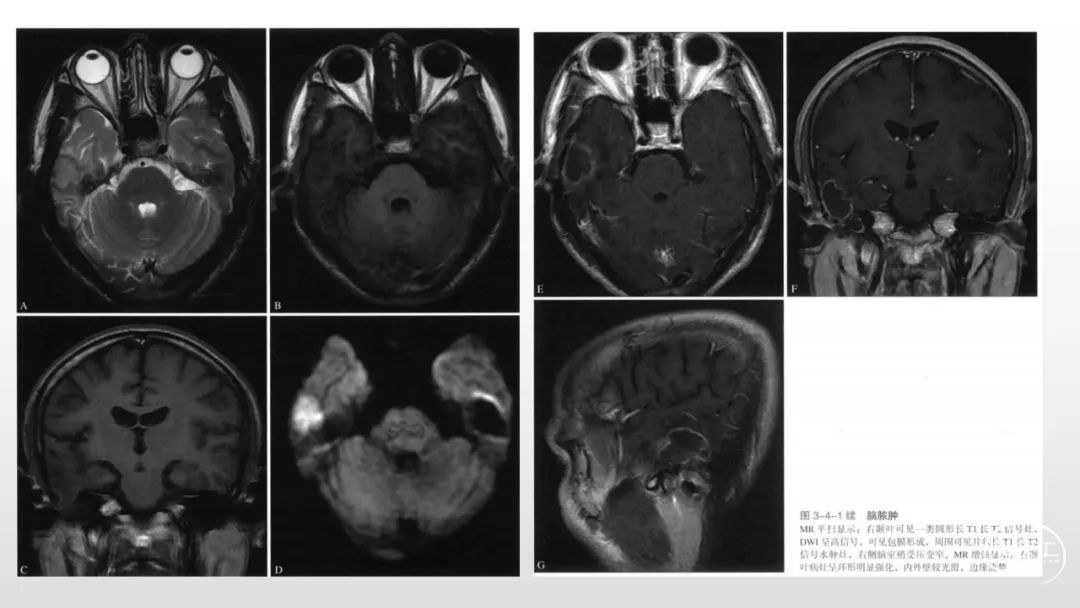

颅脑影像诊断基础知识讲座:感染和免疫性疾病1